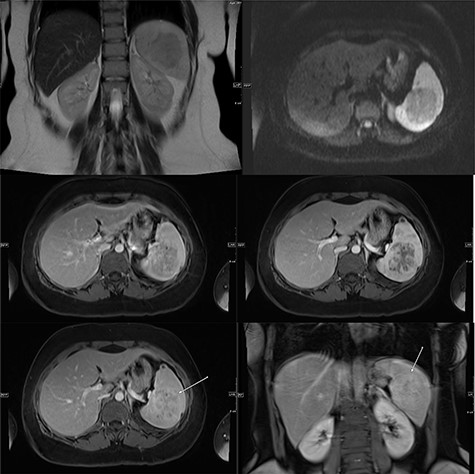

A repeat contrast-enhanced CT scan 21 months later showed an increase in size of the lesion to 8.0 × 7.2 × 6.6 cm (Fig. 4). Positron emission tomography (PET) CT demonstrated the mass to be moderately hypermetabolic with a standardized uptake value (SUV) of 4.7 (Fig. 5).

The post-contrast CT axial image showing central hypodense splenic lesion in portovenous phase (arrow—right image) which becomes isodense on delayed images (arrow—left image).